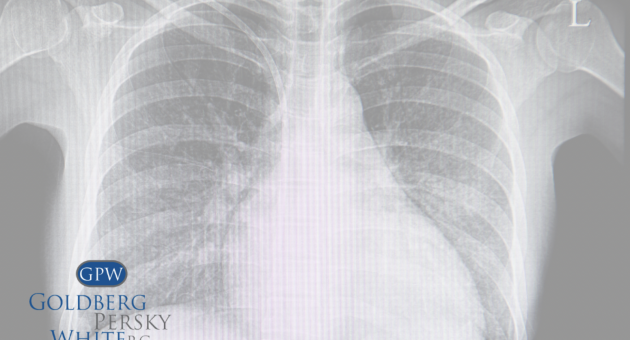

Lung Cancer Awareness Month 2022

Lung Cancer Awareness Month 2022 November is Lung Cancer Awareness Month. There are two types of lung cancer: non-small cell lung cancer and small cell lung cancer. Most cases, around 80 to 85 percent of lung cancers, are non-small cell. It can be broken down into adenocarcinoma, squamous cell carcinoma, and large cell carcinoma. These […]

Mesothelioma Awareness Month 2022

Mesothelioma Awareness Month 2022 September is Mesothelioma Awareness Month. Mesothelioma is a rare cancer of the mesothelium, which is a thin membrane that lines different areas of the body. The four types of mesothelioma include: pleural, peritoneal, pericardial, and vaginalis testis which affect the linings of the lungs, abdomen, heart, and testicles respectively. There are […]